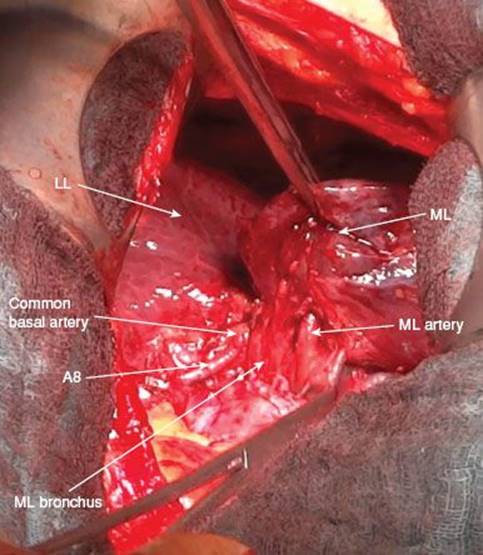

Dissection of Bronchus

Removal of the lymph nodes in the interlobium (station 11) also gives a better exposure of the middle lobe bronchus which lies posteriorly to the middle lobe artery (Fig. 11.9). The bronchus originates from the intermediate bronchus just opposite of the bronchus to the apical segment of the lower lobe (B6). Once the middle lobe artery is transected, the bronchus is clearly visible. It is a rather small structure with the typical cartilaginous impression when palpating. By pulling the middle lobe anteriorly, the bronchus can be identified by placing it between the thumb and index finger. In general the external diameter is not larger than 6 to 7 mm.

Figure 11.9 Exposure of middle lobe bronchus and middle lobe artery which run parallel.

Concerning the anatomy of the middle lobe, there are some characteristics which are important to know by any thoracic surgeon. The arteries to the middle lobe originate from the interlobar part of the pulmonary artery, mostly as two separate arteries (A4 and A5). The arteries are encountered when dissecting the interlobium caudally to the branching of the anterior pulmonary truncus (A1–3) but prior to the origin of the ascending A2. Sometimes there are variations in the form of just one middle lobe artery or a middle lobe artery originating more distally in the interlobium. In rare cases one branch of the middle lobe artery comes off the artery to the anterobasal segment (A8).